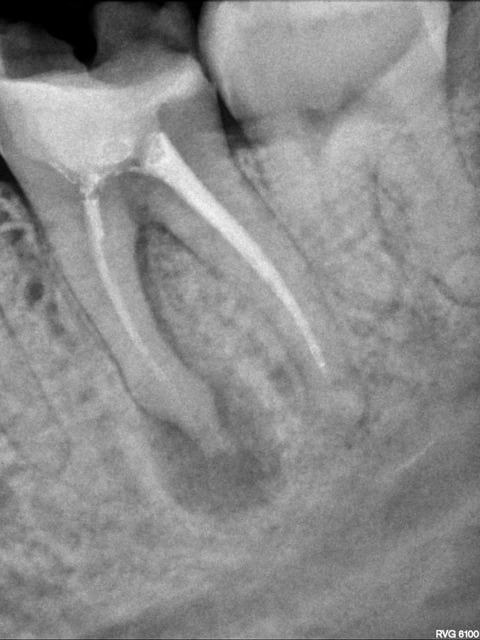

Voici les radios de l'endo exclusif. A noter la racine distale qui avait été retraitée par sa dentiste quelques semaines auparavant (la racine mésiale n'ayant pas été retraitée car elle proposait une hémisection).

J'ai éclairci l'histoire de la "deuxième couronne à 200€", car j'avais vraiment du mal à y croire ... j'ai épluché les devis, et en fait mon copain a compris que l'inlay-core à 220€ était sa prochaine couronne provisoire :D